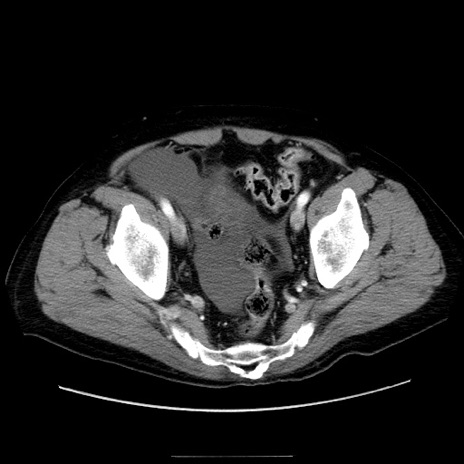

症例30(横断像)

【症例】80歳代男性

【主訴】臍周囲痛

【現病歴】約6時間前から臍下部痛が出現。次第に腹部膨隆・背部痛も生じてきたため来院。背部痛の場所は変化しない。

【身体所見】意識清明、BT 36.3℃、BP  131/87mmHg、P 87bpm、SpO2 100%(RA)、臍周囲自発痛・圧痛あり、反跳痛なし、自発痛部位に一致して板状硬あり、腹部膨隆、腸雑音減弱、CVA tenderness両側陰性。